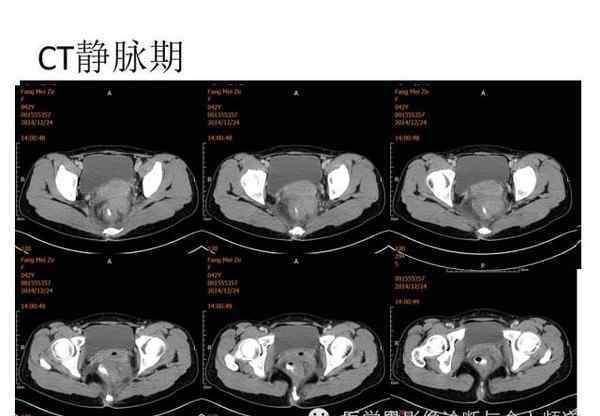

[图片图片]

[图像特征]

核磁共振平片扫描和增强扫描显示:

盆腔内可见弥漫性长T1长T2异常信号,FS-T2WI可见高信号,涉及直肠左前壁、直肠侧韧带和宫颈等。边界不清,盆腔可见条带状FS-T2WI高信号强度。注射钆喷酸葡胺后,病情明显加重。

CT对女性盆腔炎性包块的诊断价值

虽然女性盆腔炎性包块在临床上有一定的特点,但有时很难发现病变并进行鉴别诊断。CT在鉴别肿瘤病变中起着重要作用,为治疗方案的选择提供了依据。CT诊断对于确认盆腔炎的存在具有重要意义,尤其是对于高位、大范围或腹膜后脓肿形成的病例。它可以明确疾病的部位和累及范围,为制定手术方案提供有力的依据。因此,本文认为在盆腔炎症性病变与其他占位性病变难以鉴别时,有发热、下腹痛病史时,常规妇科检查不清,疑有盆腔脓肿。